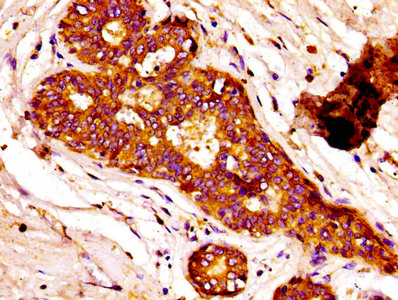

IHC image of CSB-PA13179A0Rb diluted at 1:100 and staining in paraffin-embedded human breast cancer performed on a Leica BondTM system. After dewaxing and hydration, antigen retrieval was mediated by high pressure in a citrate buffer (pH 6.0). Section was blocked with 10% normal goat serum 30min at RT. Then primary antibody (1% BSA) was incubated at 4°C overnight. The primary is detected by a biotinylated secondary antibody and visualized using an HRP conjugated SP system.